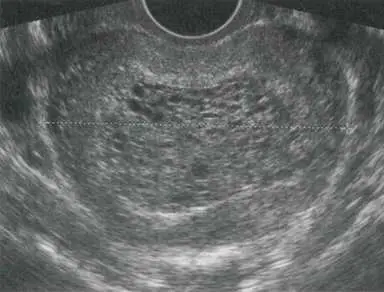

25 歲女性因最近一天內出現大量陰道出血而來到急診就診,這位女性自述:最近一週出現嚴重噁心感、最後一次月經開始日為 6 週前、自行驗孕尿液懷孕試驗呈陽性反應,到急診時,其血壓為140/90 mmHg、心跳 每分鐘 120下,身體理學檢查發現其子宮大小約為懷孕 12 週、子宮頸長度正常且子宮頸口關閉未開,抽血檢驗發現血清β-人類絨毛膜刺激激素(β-subunit human chorionic gonadotro pin, β-hCG)值為 400,000mIU/mL,骨盆腔超音波檢查發現如圖所示:在子宮腔內充滿雜回音性的(mixed echogenic) 組織且伴隨很多的低回音性的囊狀間隙(anechoic cystic spaces)、似暴風雪狀(snowstorm appearance)、看不到羊膜囊或胎兒發育。下列何者為最正確的診斷?

經骨盆超音波可見:整個子宮腔充滿混合回音性組織,伴隨多數無回音之囊狀空隙,呈現「雪暴」(snowstorm)或「葡萄串狀」(bunch-of-grapes)外觀,找不到羊膜囊、胚胎或胎心搏動。此影像即complete mole最具特異性的超音波表現,代表絨毛水腫性變及滋養層過度增生,整個子宮腔被水泡狀絨毛團塊所佔據 (radiopaedia.org)。